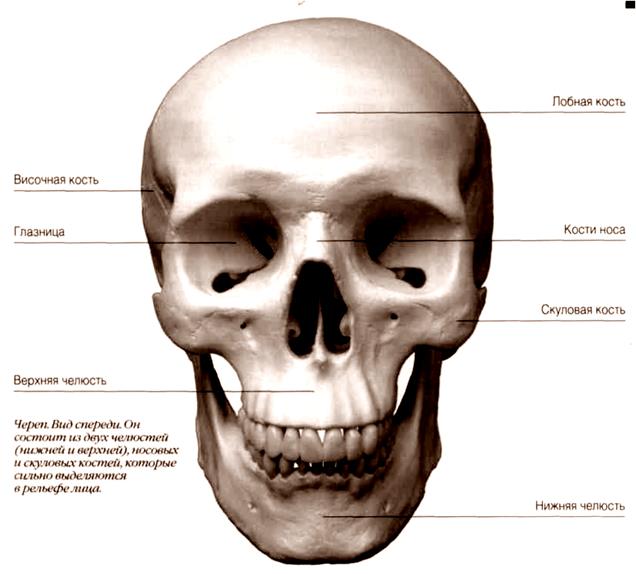

Анатомические изображения срединной сагиттальной линии черепа